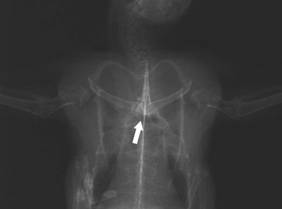

Torn ligament

between humerus and shoulder joint. Observe the dislocation

of the left humerus head of the shoulder joint |

A defect in the shoulder

girdle can be diagnosed by the bird’s inability to fly or only in a

restricted way, an incongruent movement of wings, or the shoulder

concerned hanging down, as well as the inability of the Swift to

turn round on its own accord when you try and put it on its back. An

x-ray is essential in order to exclude the possibility of bruising.

An exact positioning is indispensable for an impeccable picture of

the shoulder girdle area. If necessary, sedating the patient may be

advisable.

The shoulder girdle

defects occurring most frequently are fractures of the clavicula and

the coracoid as well as the luxatio articulatio humeri (shoulder

luxation), which clinically shows itself in the same way and can be

clearly diagnosed in the x-ray: the very often significant

dislocation of the upper arm as well as the clearly enlarged

distance between the humerus head and shoulder joint of the side

concerned are visible. It is harder to diagnose luxatio art.

sternocoracoidea, which is not so infrequent: the sinewy attachment

of the coracoid to the breastbone is torn off with a dislocation

beyond the median. This defect can easily be overlooked on the x-ray

and requires a trained eye.